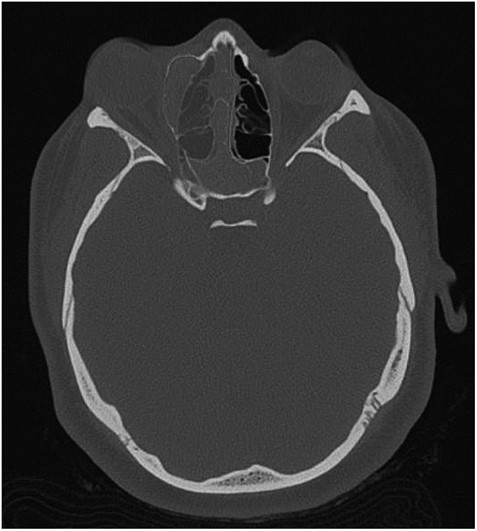

Axial CT view of the ethmoid labyrinth with the left side super imposed on the right side over the midline for comparison.

AFS is a known risk factor for development of nasal polyps [5, 6]. Incidences of AFS causing unilateral proptosis have also been described in the literature [7, 8]. The findings from the current CT, however, indicate a unique developmental process. When compared to the patient’s left side, the extent is easily seen (Fig. 3). In consideration of the preservation of the ethmoid architecture along with the patient’s age, it appears that due to the severity and duration of the polyposis and AFS, the ethmoidal labyrinth malformed while still in development. Contrastingly, in cases of several nasal polyposis, including those with ocular involvement, bone erosion and destruction are most frequently seen with respect to changes in bone anatomy [9]. Chronic remodeling of the ethmoid bone has been described in venous malformations [10], however, cases of nasal polyps leading to bone malformation are significantly underrepresented in the literature. CT imaging proved the most valuable diagnostic tool in examining the extent of the proptosis secondary to polyposis, as well as describing the changes in the ethmoid labyrinth structure. Surgical approach proved effective in reducing the patient’s symptoms, as well as confirming the etiology of the unilateral proptosis.